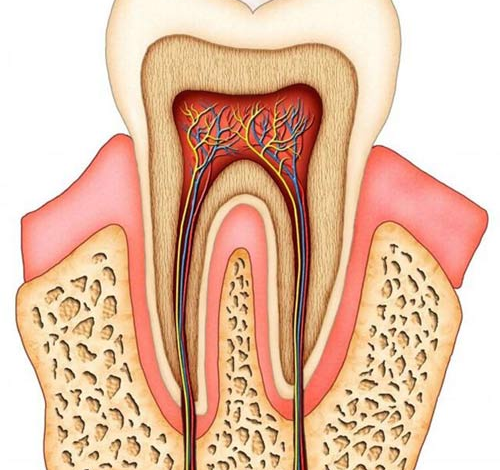

عفونت زمانی اتفاق میافتد که باکتریها از طریق پوسیدگی، ترک یا ضربه وارد پالپ (مغز دندان) میشوند. پالپ، بافت زندهای شامل عصبها و عروق خونی است که در صورت عفونت، به شدت آسیب میبیند. در صورت عدم درمان، این عفونت میتواند به:

عفونت ریشه دندان یا “Endodontic Infection” معمولاً زمانی رخ میدهد که باکتریها از طریق پوسیدگی یا ترک وارد پالپ (بافت نرم داخل دندان) میشوند. اگر این عفونت درمان نشود، میتواند به بافت اطراف ریشه گسترش یافته و حتی باعث آبسه دندانی شود.